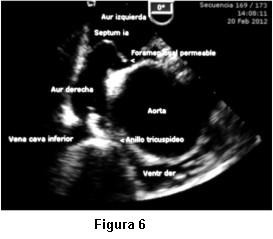

Dada la persistente sospecha clínica de un shunt de derecha a izquierda no detectado por el ETT, se nos solicitó la realización de ETE. Las imágenes transtorácicas pre ETE fueron claras en mostrar una raíz de aorta dilatada, ocupando gran parte de la AD y comprimiendo el anillo tricuspídeo (figura 5). Insuficiencia aórtica moderada. VD colapsado. Flujo a través de válvula tricúspide de difícil detección, no valorable por Doppler. Arteria pulmonar no dilatada. Se realizó inyección de suero agitado y se comprobó masivo pasaje de microburbujas hacia cavidades izquierdas. El ETE mostró adicionalmente un septum interauricular deformado, con un foramen oval persistentemente abierto, hacia el cual se observaba flujo direccionado desde vena cava inferior, lo cual producía un muy severo y constante cortocircuito de derecha a izquierda. Raíz de aorta y aorta ascendente dilatada (44 y 47 mm) con elongación de aórtica torácica. Severa compresión de anillo tricuspídeo por aorta ya descripta (figura 6).